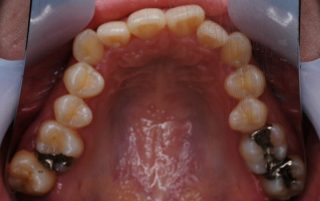

このケースは、デコボコでの相談のケースです。この患者さんでは、真ん中のあたりの歯を4本抜歯して、綺麗に歯並びを並べました。治療期間は、約2年間です。ホワイトワイヤーを用いたマルチブラケット矯正法で治療しました。

- ①治療期間:約2年(約26回)

- ②費用:約90万円(税別)